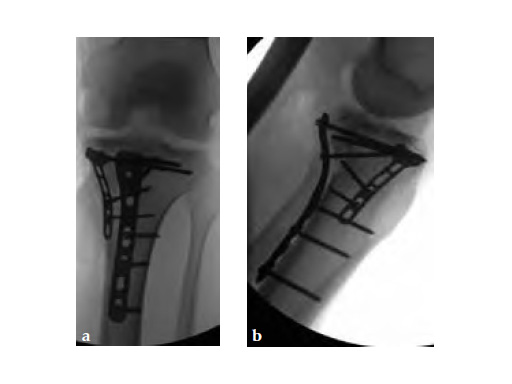

The system consists of six anatomically precontoured plates (1, 2, 4, 6, 8, or 10 shaft holes) with a range of six lengths (72-186 mm). The low profile plate head limits soft-tissue irritation and features four locking holes; one slotted for ease of plate positioning. The 3.5 mm LCP holes in the shaft enable fixation of posteromedial fragments with locking or non-locking screws.

Initially taken for incision and drainage and then ORIF . Patient placed in a floppy lateral position with the effected lower extremity externally rotated (opposite hip and shoulder bumped up about 3040) allowing exposure of the posterior medial knee. A posterior medial and an anteromedial incision were used to repair the fracture with a 67 cm skin bridge.

Postoperative healing was uneventful and the patient had no complications.